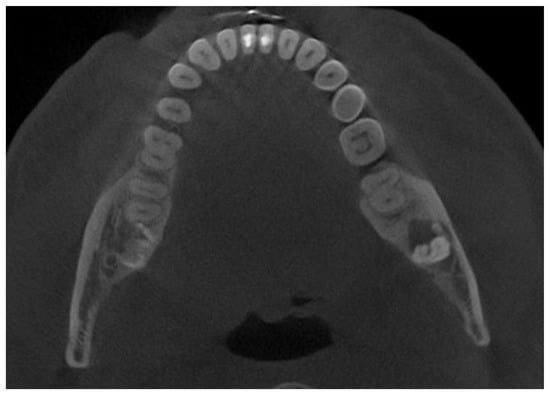

The patient was a generally healthy male without any history of surgery, illness, or surgery in the oral cavity region. The occurrence time of this lesion and its growth duration were not established. All of the surrounding anatomical areas and spaces were free of any diseases. Routine panoramic radiography (panx) and cone-beam computed tomography (CBCT) excluded any major changes in the bone near the tumour and excluded any potential odontogenic cause of the MRT swelling. The cortical parts of the bone in the CBCT study were also normal. No bone erosions, infiltrations, tooth resorptions, or bone swelling were detected (Figure 3). Because of the lack of substantial bone involvement, except for the impacted right mandibular wisdom molar with visible signs of bone ankylosis, suspicion of a nonodontogenic tumour was established.

Figure 3. Cone-beam computed tomography in the sagittal plane before biopsy. The superior part of the cortical bone remained clear and intact without any lesion or perforation.